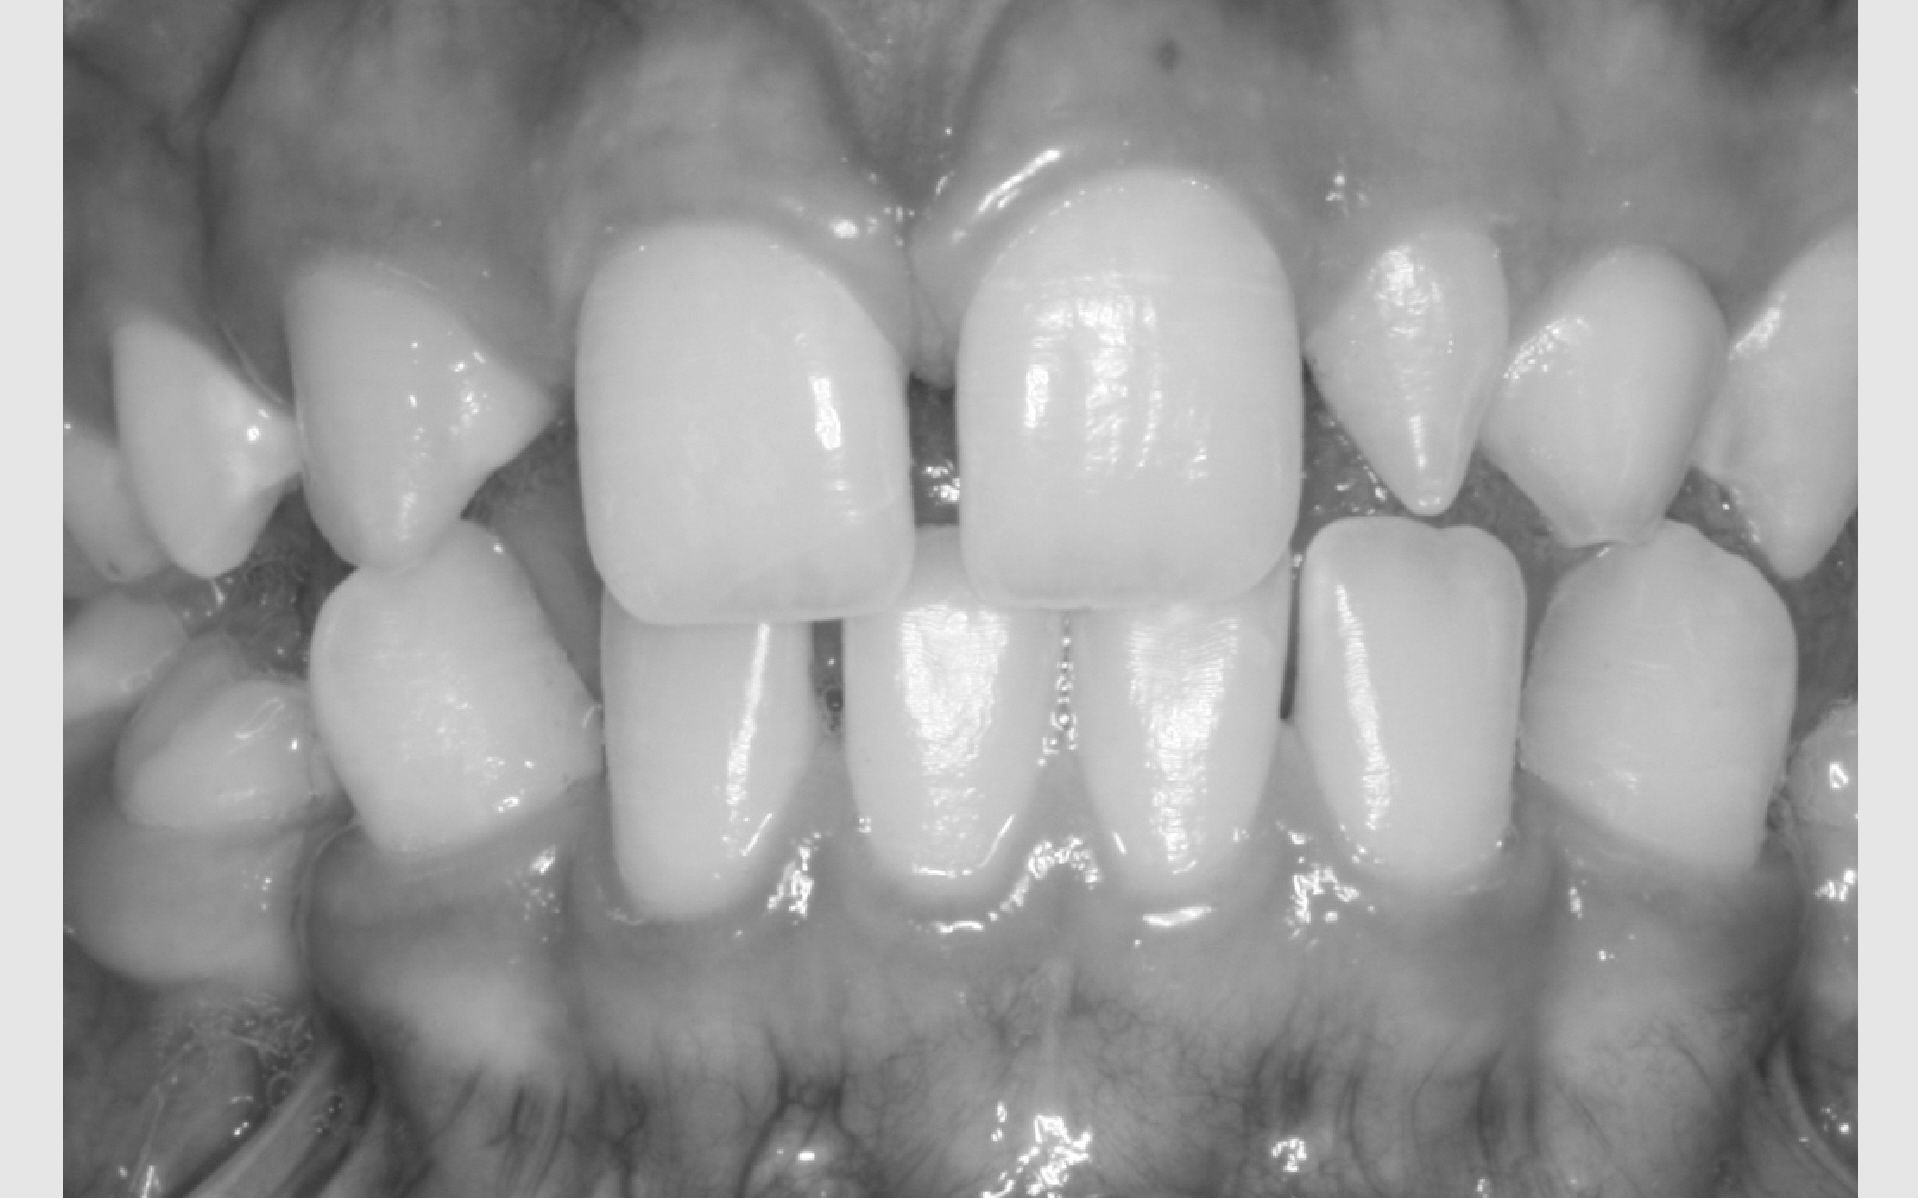

Der kan være forskellige grunde til, at et barn eller en ung får tilbudt bøjlebehandling. De hyppigste grunde er:

• Misforhold mellem kæber: stort overbid eller underbid

• Ekstrem pladsmangel

• Fejllejrede tænder, der giverrisiko for skader på andre tænder

• Manglende tænder

Som udgangspunkt tilbydes barnet/den unge behandling, hvis der er risiko for nedsat funktion ved udeladt behandling.